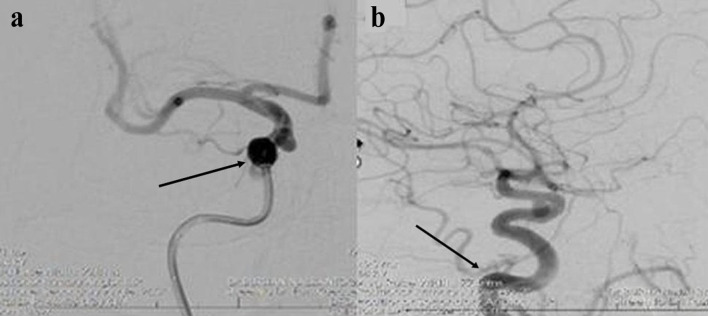

面肌痉挛(HFS)是一种神经系统疾病,其特征是面部一侧面神经支配的肌肉不自主、阵发性收缩。虽然原发性HFS最常由面神经根出口区(REZ)的血管压迫引起,但继发原因如肿瘤、动静脉畸形和颅内动脉瘤是罕见的。由于动脉瘤压迫导致的HFS的治疗仍然具有挑战性,并且关于血管内治疗的文献,特别是流分流支架的文献是有限的。我们报告一例56岁女性,有2型糖尿病、高血压和高胆固醇血症病史,表现为进行性右侧HFS。影像显示右侧颈内动脉(ICA)在海绵状眼段有囊状动脉瘤。患者成功接受了衍生栓塞装置(DED)血流分流支架的血管内治疗。她的HFS在手术后完全消失,在6个月的随访中没有神经功能缺损或复发。本病例强调了分流支架置入术治疗由ICA囊状动脉瘤引起的HFS的疗效,是北塞浦路斯第一例此类报道。该病例强调了考虑非典型HFS继发病因的重要性,并证明了在这种情况下血管内血流转移的治疗潜力。

Hemifacial spasm (HFS) is a neurological disorder characterized by involuntary, paroxysmal contractions of the muscles innervated by the facial nerve on one side of the face. While primary HFS is most often caused by vascular compression at the root exit zone (REZ) of the facial nerve, secondary causes such as tumors, arteriovenous malformations, and intracranial aneurysms are rare. The management of HFS due to aneurysmal compression remains challenging, and the literature on endovascular treatment, particularly with flow diverter stents, is limited. We report the case of a 56-year-old woman with a history of diabetes mellitus type 2, hypertension, and hypercholesterolemia, who presented with progressive right-sided HFS. Imaging revealed a saccular aneurysm of the right internal carotid artery (ICA) at the cavernous-ophthalmic segment. The patient underwent successful endovascular treatment with a Derivo embolization device (DED) flow diverter stent. Her HFS resolved completely post-procedure, with no neurological deficits or recurrence at 6-month follow-up. This case highlights the efficacy of flow diverter stent placement for HFS caused by ICA saccular aneurysm and represents the first such report from Northern Cyprus. The case underscores the importance of considering secondary etiologies in atypical HFS and demonstrates the therapeutic potential of endovascular flow diversion in this context.